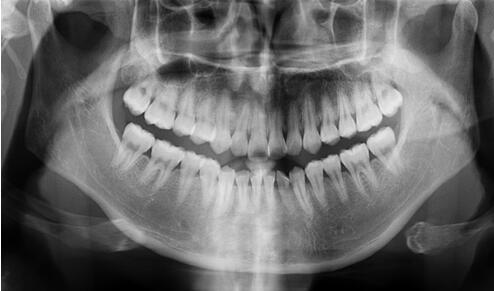

全口曲面斷層片

看似復(fù)雜,用人話說就是口腔牙齒的X光片。

牙醫(yī)通過對這張片的分析,能找出潛藏的牙周疾病問題、牙根發(fā)育等情況。通常是否拔牙、拔哪個(gè)牙、怎么拔,就是靠它了!